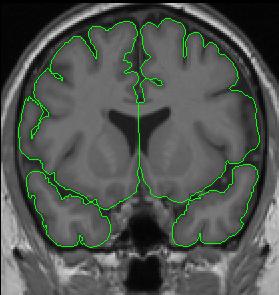

The cerebral hemispheres are extracted independently, and their division, is most clear in slices where they are completely separate.

When corpus callosum is present, it is necessary to separate the hemispheres by manually drawing along the midline.

Anteriorly, when the temporal lobes are present but not connected to the frontal lobes, the temporal lobes are extracted separately from the frontal lobes. Thus, you will have four separate outlines that make up the cerebral exteriors.